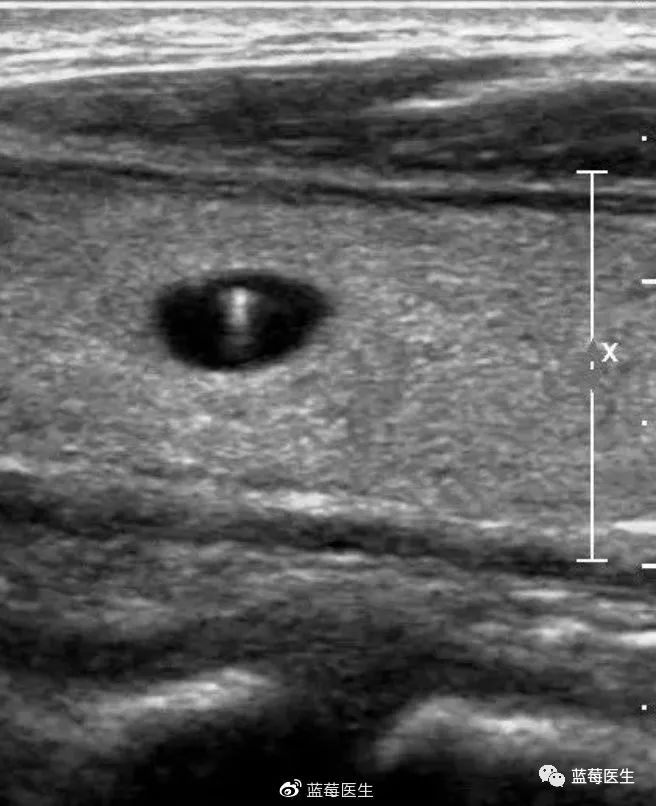

关于胰腺实性假乳头状肿瘤的特征,这病年轻人尤其女性更容易中招,平均年龄33岁左右。症状嘛,典型表现就是腹痛,但确实没啥特异性。CT检查会显示边界清晰的囊实性肿块,实性部分会慢慢强化,有时还能看到钙化点。